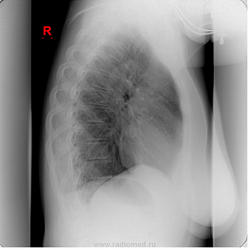

Чистый профосмотр

. Что-то задерживает взгляд. Что же?

Навскидку- глаз не зацепился.

Согласна с Любой- странно расширенный участок трахеи.

Трахеобронхомегалия?

Боковую проекцию в студию.

Не-не. Сегодня не 1 апреля. Всё внимание верхнему средостению.

Могу добавить заднюю и боковую проекцию. И снимки прошлых лет. Что предпочтительнее?

Добавил две проекции.

Что-то не то с задним опорным комплексом верхнегрудных позвонков. Ламинэктомия как-будто?

Мы же угадываем? Пусть будет экстирпация гортани.

Гриша Хата сегодня просто отличник!

10 лет назад: Опухоль гортани T3N1M0. Расширенная ларингэктомия + лимфаденэктомия справа; Лучевая терапия.

И, как видим, без рецидива и процедива.